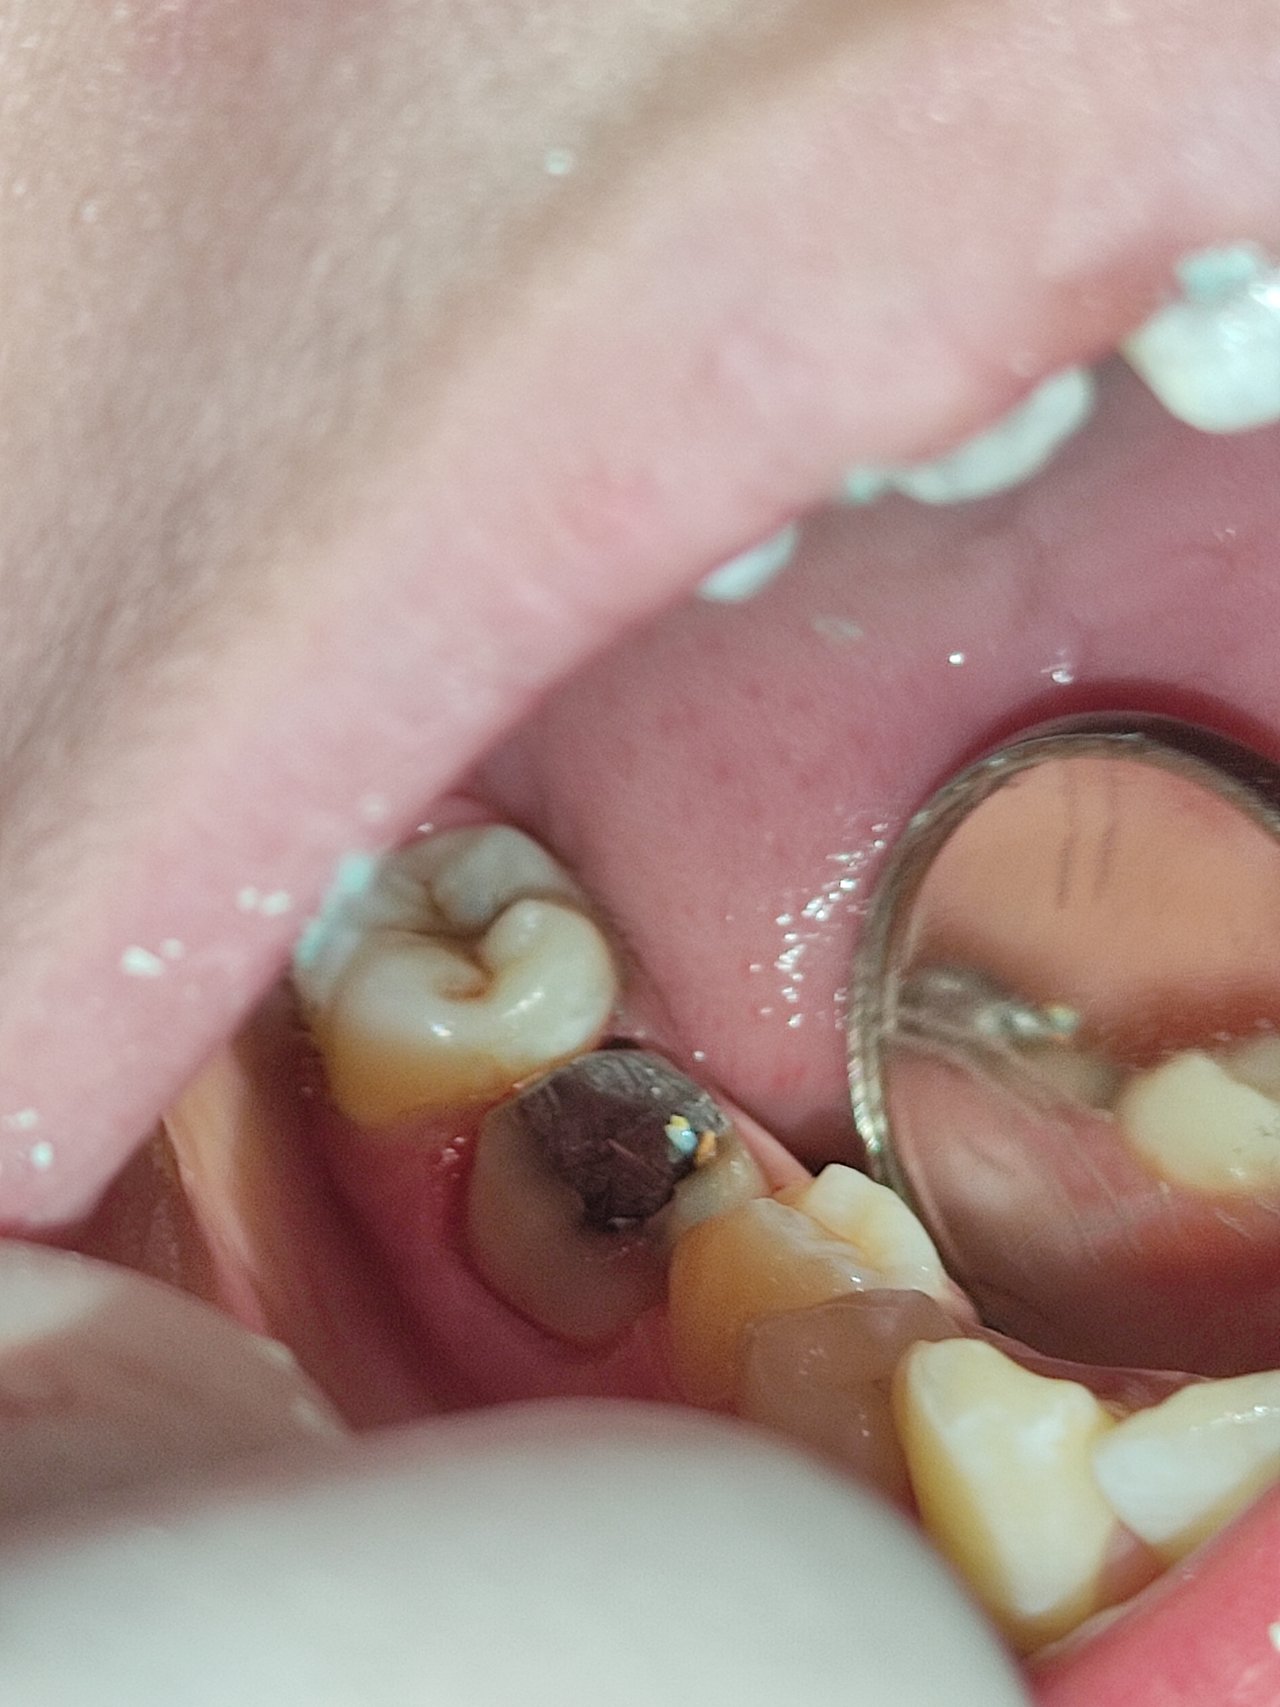

CASE: UNCAPPED ROOT CANAL TREATMENT OF LOWER 6

Picture clicked with patient's consent

A patient headed into the OPD with a complain of uncapped Lower 6. By lower 6 here we mean the Mandibular Molar. She had her Root Canal Treatment recently and the dentist had left her tooth uncapped which means the crown wasn't fixed. Now in these situations, it is very important to set the cap on the untreated tooth to avoid and bacterial colonization and some serious infections.

The first prognosis is done by tapping the tooth with a tooth mirror to observe whether the patient has any pain or not. After that the patient is asked to have an X-ray of their tooth so that we can see if there's any infection which might have penetrated to the root or if the root is distorted in any way. If the X-ray looks fine then the on duty dentist is in charge of the ongoing case.